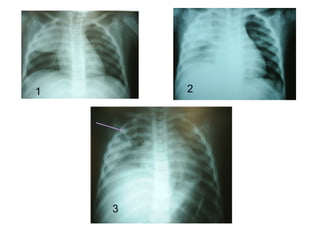

 Derrame pleural

 Pneumatoceles

 Pneumotórax /piopneumotórax

 Pneumonia necrotizante/Abscesso pulmonar

outras.

Complicações

1 2

3